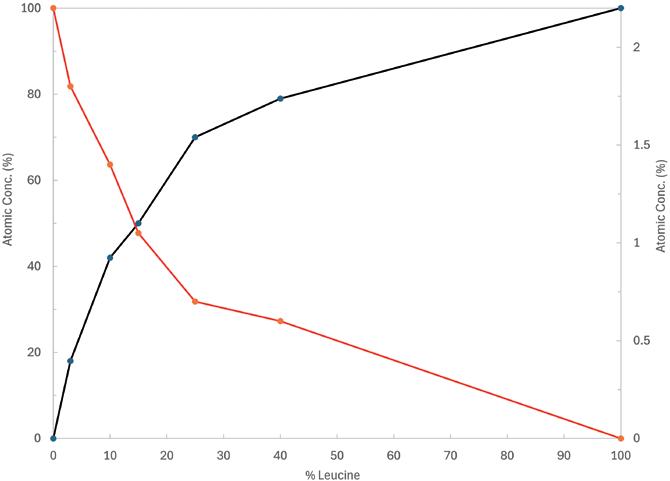

Generally, biologics are therapeutic proteins derived from living systems (such as bacteria, yeast, plants or animals) or blood that differ from “small molecules”, which are synthetic, or plant derived (see Figure 1). Examples of biologics include vaccines, growth factors, monoclonal antibodies and immune modulators. With their high target specificity and comparatively low toxicity, biologics are one of the fastest-growing therapeutic classes in the pharmaceutical industry.

Figure 1: Comparison of three different classes of biologic drugs with a typical small molecule. (Adaptation from Revers L & Furczon E, Canadian Pharmacists Journal, 2010.)